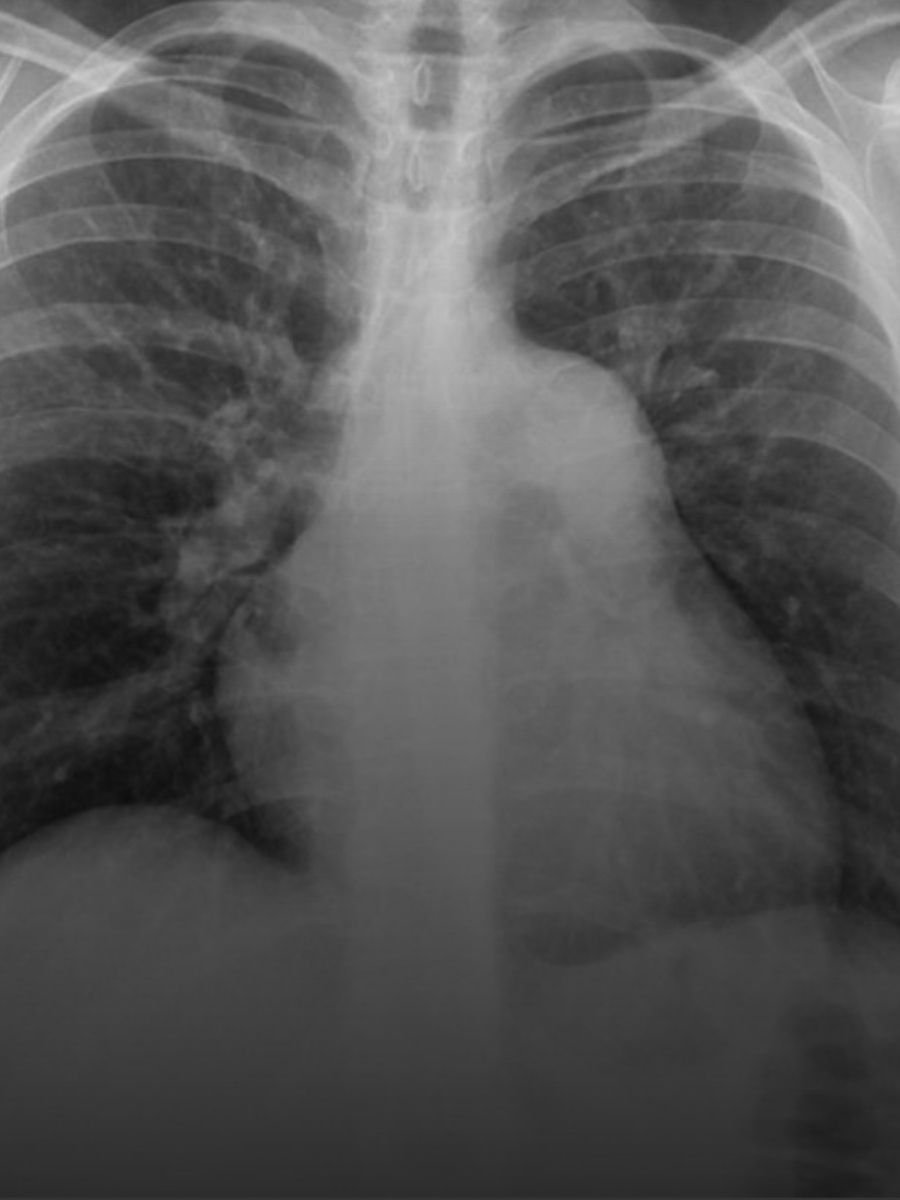

Cateterismo Derecho

Es una intervención diagnóstica que se usa para medir la presión en la arteria pulmonar y así valorar si el paciente sufre de hipertensión pulmonar o no, y en algunos casos, determinar la causa de la hipertensión pulmonar.